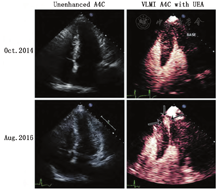

虽然在2008年的ASE专家共识声明中就已经提到了VLMI多脉冲序列方案在多数系统上都可用[1],但最近才有制造商开始将它们用于LVO。VLMI技术最初是为心肌灌注评估而设计的,但它们对于微泡检测的敏感性和无漩涡伪影的心尖部心腔的完整造影显示对负荷LVO成像有很大的帮助。多中心和前瞻性单中心研究均证实了VLMI成像可以有效地检出RWM异常[16,45,66]。除了增强敏感性和心尖部的勾勒之外,VLMI技术还可检测负荷试验时透壁室壁增厚无法检出异常的心内膜下室壁增厚异常情况[42,66]。结合LVO以及高机械指数脉冲破坏后的心外膜层再充填过程有助于勾勒心内膜边缘和分析该处室壁增厚(图5和视频7;在www.onlinejase.com获取)。将UEA与VLMI成像用于室壁增厚和缺血的评估,并结合多巴酚丁胺负荷超声心动图对左束支传导阻滞患者进行常规评估,被证明可提高CAD的检出,并可独立预测死亡率和心血管事件[67]。

很明显,这些研究基础显示UEA提高了静息和负荷成像过程中RWM分析的诊断准确性。VLMI成像对于RWM分析来说似乎是最佳的,原因在于灌注数据带来的增量价值,有助于区分因心内膜下缺血引起的轻微的室壁增厚异常。这似乎对所有冠脉支配区域都有帮助,尤其是通常难以显影的节段(图6,视频4和7;在www.onlinejase.com获取)。由于冠脉支配区域的疾病可能只影响心尖或胸骨旁切面的某个特定节段,因此当任何节段无法充分可视化时,写作组建议应用UEA进行LVO检查。